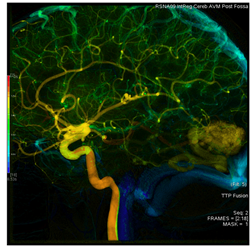

AngioViz uses peak time and density with color as time, and peak density as brightness to show contrast flow timing and magnitud

In one image, AngioViz can show peak pixel density value over an image series. This can indicate relative contrast density and d

AngioViz can show the time that each pixel reaches peak density on a color coded time scale. This helps indicate contrast flow t

A New Visualization of Vascular Flow

AngioViz provides a new visualization of the vascular flow seen in DSA imaging, utilizing a technique called parametric imaging. AngioViz looks at each pixel in the image series and determines two things — the peak value of opacification caused by the contrast, and the time it takes for that pixel to reach peak opacification. These two parameters can be displayed as separate images or combined into a single color-coded image that represents parameters of vascular flow. This enables doctors to perceive parameters of flow quickly to support decision-making. In addition, AngioViz allows easy comparison of parametric images from different DSA acquisitions, such as pre- and post-treatment images. This can help physicians understand the impact on flow dynamics of various interventional treatments.